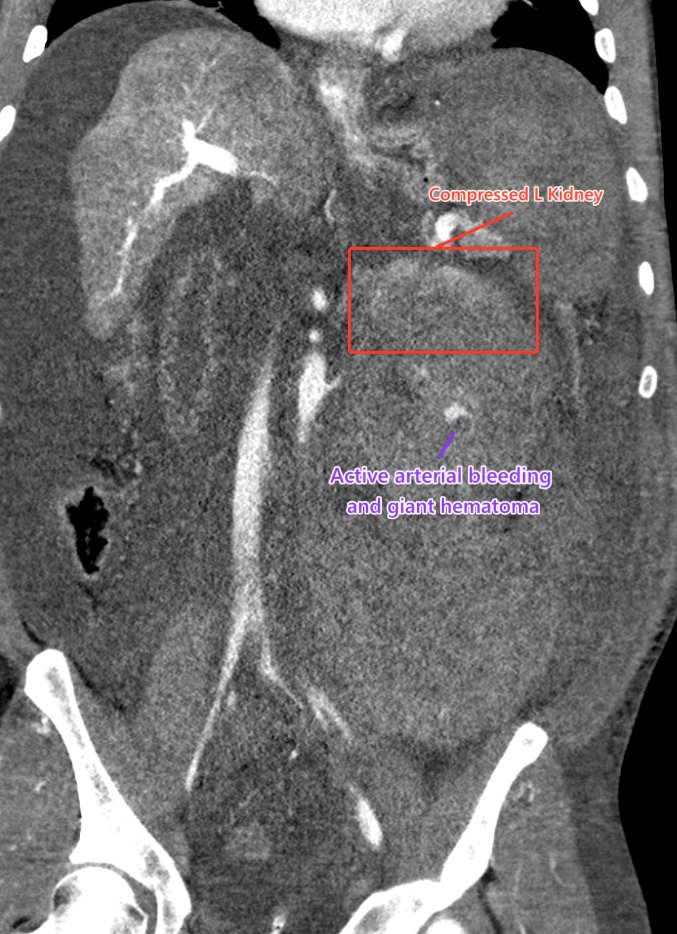

58 year old cirrhotic patient, underwent renal biopsy at outside facility. 1 day of progressive abdominal pain. CT with active bleeding from biopsied kidney.

#IRad quick to#embolize the vessel and#stopthebleed#MIIP#InnovationToHeal#Radiology#TwittIR#IRadRes pic.twitter.com/8GcA0rVLtE